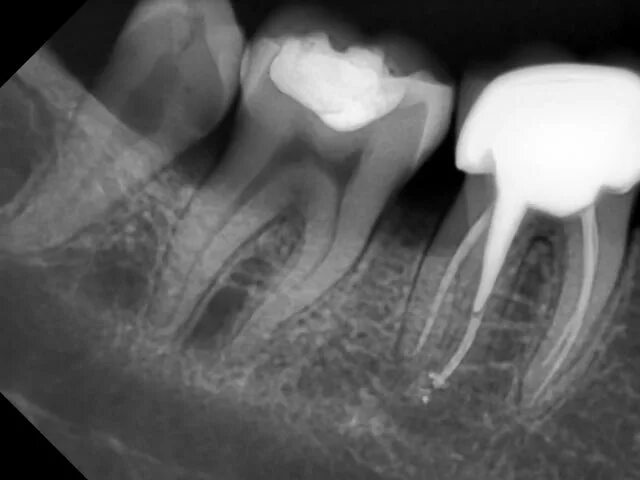

Киста зуба что это